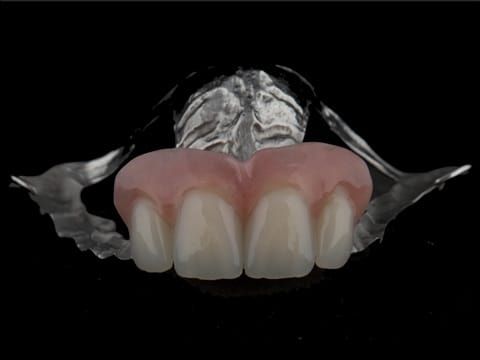

- Extract the upper 2-2 teeth and replace with an interim acrylic based partial denture. Reline the interim denture over 9 - 12 months, replacing with a definitive cobalt chromium based partial denture. The definitive denture would ideally be designed as an occlusal protective splint to reduce the the potential for mechanical wear and breakages of the moderately/heavily restored maxillary dentition. In addition, should further upper teeth require extraction they could be added on to the denture cobalt chromium framework - therefore a new prosthesis would not be required as future teeth are lost. This option would produce an excellent aesthetic outcome. This is the option the patient chose to have.

Following consultation and second discussion appointment the patient chose to have option 3 namely, a maxillary cobalt chromium based partial denture/protective occlusal splint. The clinical situation and treatment process is shown in detail below with photographs. The patient was successfully rehabilitated with this and her quality of life considerably improved. The clinical work was provided by Finlay and the technical work by Rowan.